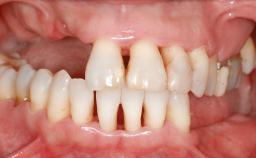

An 18-year-old man was referred for implant therapy in the posterior mandible to the Department of Oral Surgery and Stomatology (University of Bern, Switzerland). He was healthy and did not smoke. Tooth 35 was congenitally missing, involving a single-tooth edentulous space that offered an adequate mesiodistal dimension for implant placement but exhibited a typical pattern of buccal flattening. A panoramic radiograph was obtained, which revealed a sufficient vertical bone height above the mandibular canal and a normal bone structure in the edentulous area.

Bone Volume Horizontally and vertically sufficient Horizontally deficient Deficient vertically or deficient vertically AND horizontally

Bone Volume Deficient horizontally, requiring prior grafting